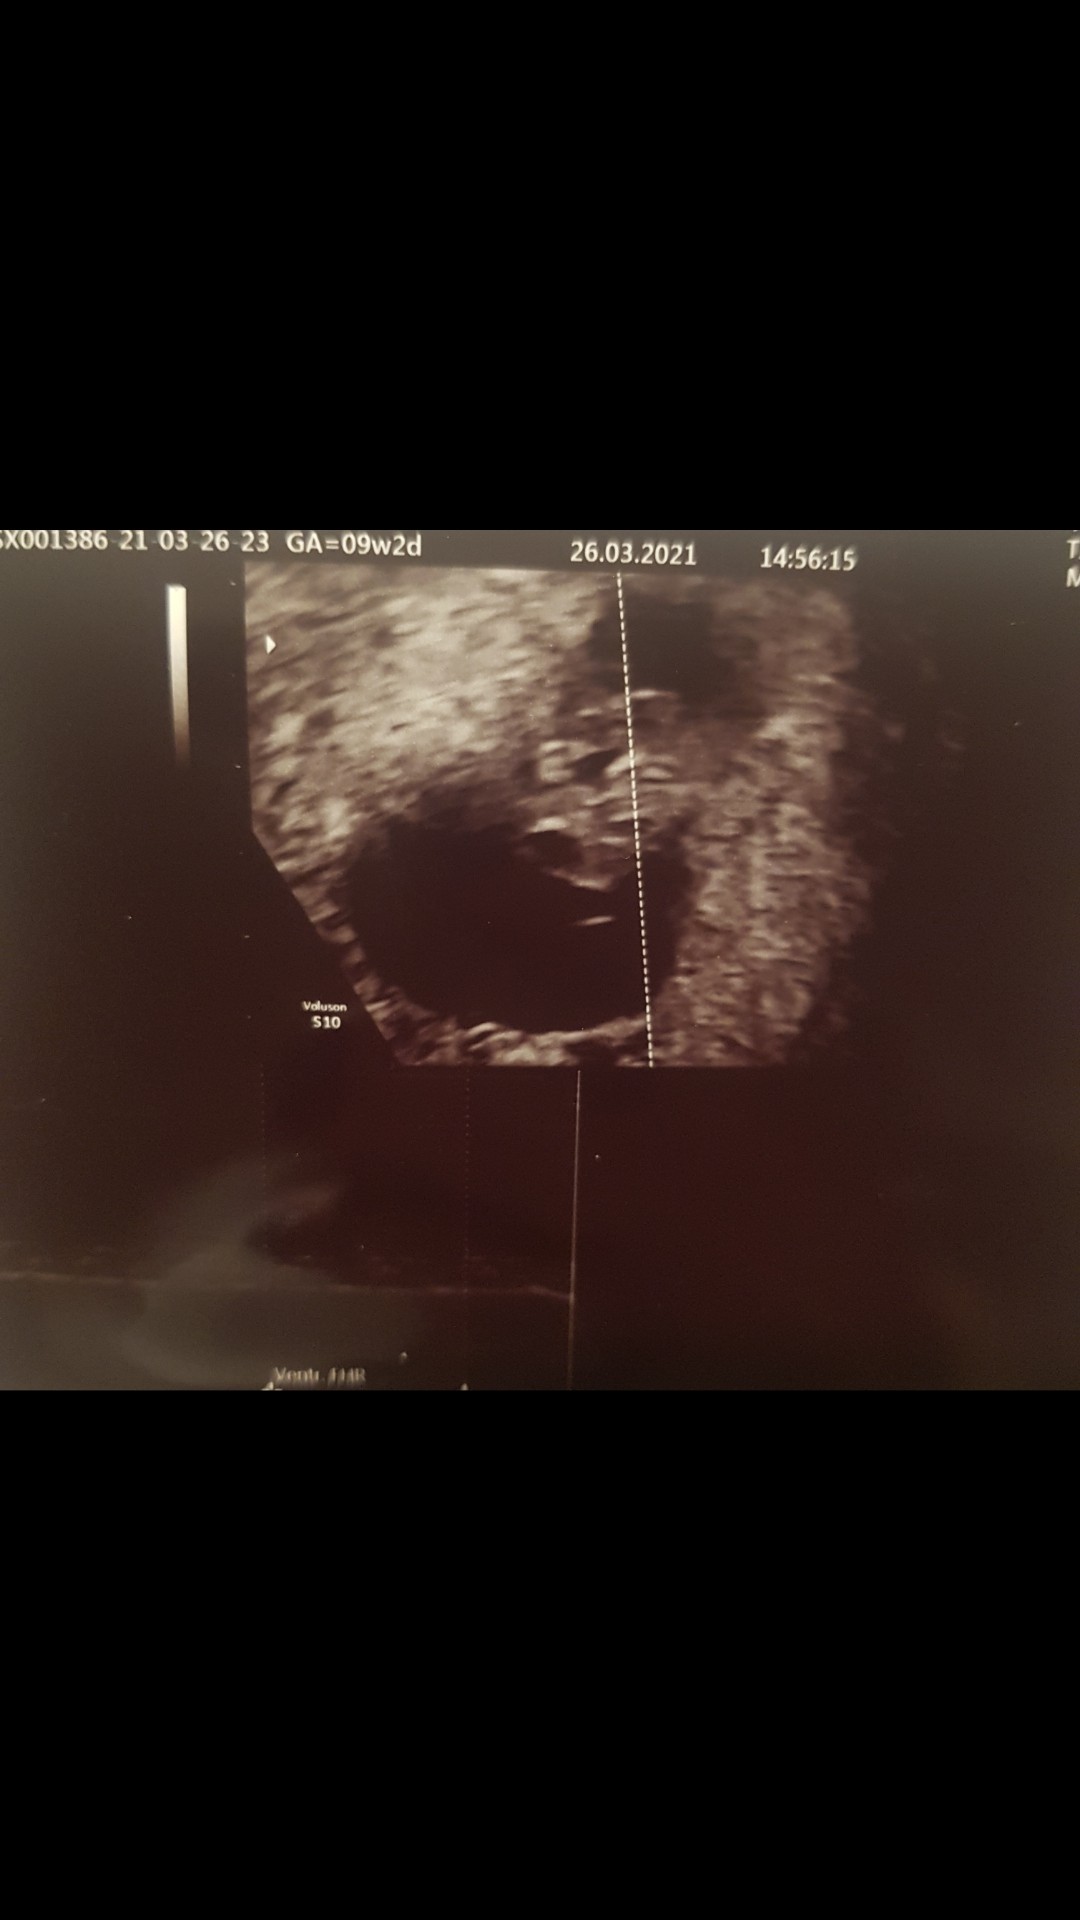

Mój bobo. Idealnie 8+1 :-) pięknie bije serduszko. Nie mogę powstrzymać łez :)

Dziś u mnie 8+1 termin na 08.11 z usg. OM 20.01 ( u mnie zawsze cykle co 35-60 dni).

Nasz kropek ma już 13mm, serduszko ładnie mu bije i póki co wszystko jest w porządku.